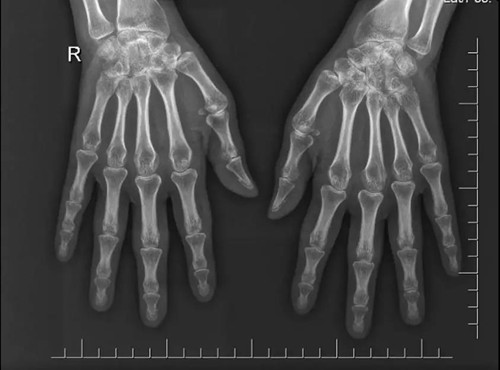

病例簡介 患者為44歲中國女性,10個月前開始出現(xiàn)多關節(jié)腫痛。查體可見患者右手近端和遠端指間關節(jié)外形呈梭形腫脹,有壓痛,雙腕關節(jié)及膝關節(jié)腫脹、壓痛,晨僵時間>30min,X線片(見圖1)示雙側手腕關節(jié)、指間關節(jié)間隙縮小。 圖1 患者雙手X線片